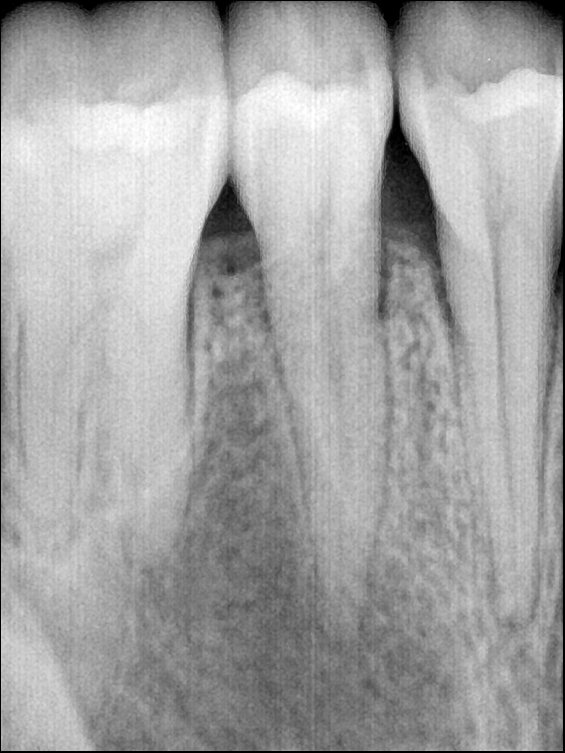

CR/DR 牙齿分割阶段记录

当前进展

- 完成了 CR/DR 牙齿相关分割训练

相关测试

遇到的问题

- 训练过程中出现过 mask 下移问题

- 部分结果会出现 box 填充异常

- mask 边缘仍然有比较明显的锯齿感